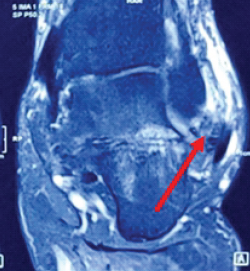

Assessment of Functional Outcome of Arthroscopic Microfractures for Osteochondral Defect of Talus

Lionel John , G Manikandan